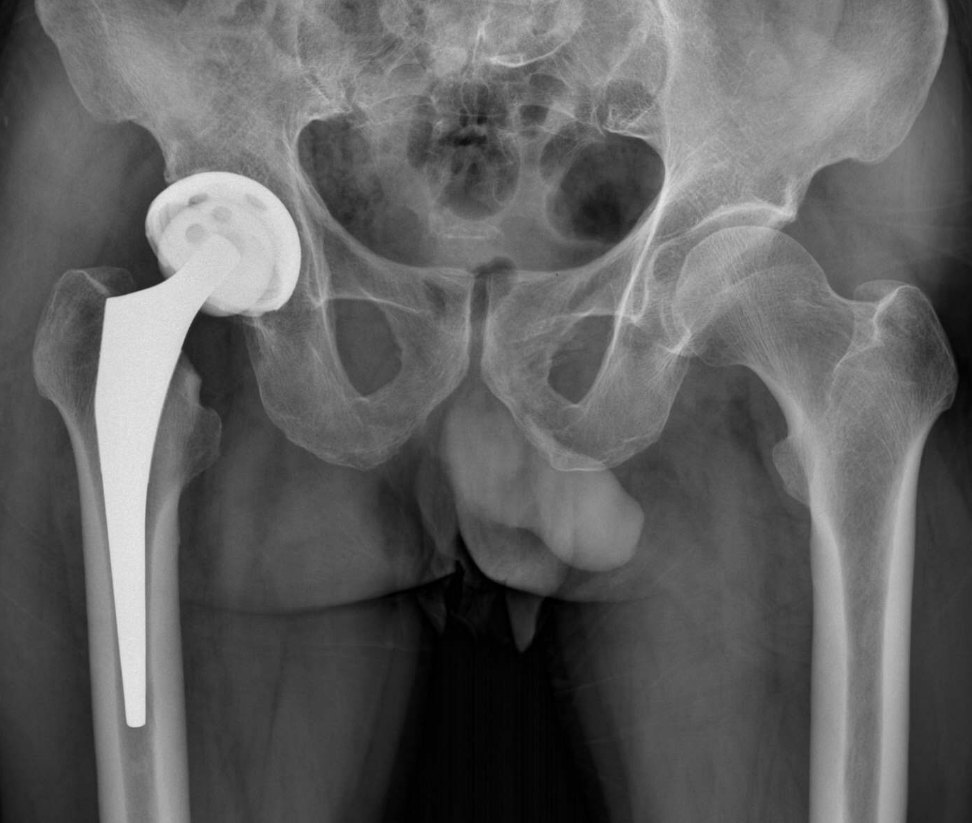

2、手術(shù)治療:對于嚴重骨頭壞死,可能需要進行手術(shù)治療,如骨移植、關(guān)節(jié)置換等,手術(shù)治療的效果因個體情況而異,需在專業(yè)醫(yī)生的指導(dǎo)下進行。